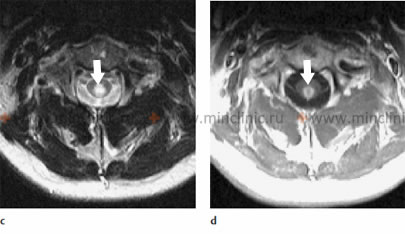

Системный саркоидоз может быть причиной поражения нервной ткани спинного мозга, что может вызывать парестезии и слабость верхних и нижних конечностей у пациента. Поражение спинного мозга саркоидозом выявляется при помощи МРТ. Проводимое лечения метилпреднизолоном и азатиоприном вызывает регресс неврологический симптоматики и восстановление нормальной морфологической картины спинного мозга.

A – На МРТ спинного мозга в сагитальной плоскости (T2 режим) выявлено гиперинтенсивное поражение спинного мозга с отёком в переделах сегментов C2-C5 и C7-Th3 (указано стрелками). B – МРТ спинного мозга с контрастированием (T1 режим) выявляет неравномерное точечное накопление контраста в спинном мозге (указано стрелками). C – Почти полное восстановление морфологической картины пораженного саркоидозом спинного мозга после лечения кортикостероидами (указано стрелкой).